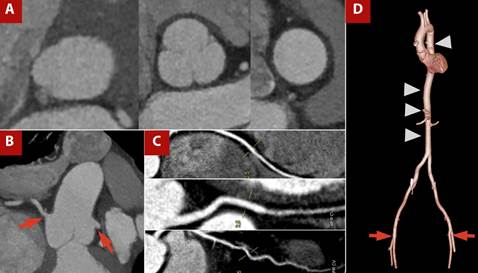

In relation to TAVI, coronary artery disease must be excluded as part of the pre-procedural protocol, and patients are usually referred for coronary angiography. However, some protocols allow coronary CT angiography to rule out significant coronary disease with adequate sensitivity and specificity. In these centers, valve and coronary assessment are performed with CT in TAVI candidates, and the need for invasive studies such as angiography is determined on the basis of these findings, an approach known as the one-step strategy. 20 Figure 3 shows an example of images acquired using the pre-TAVI protocol.

Figure 3 TAVI protocol CT angiography with a one-step approach, including coronary CT angiography. A) Orthogonal measurements at the aortic valve plane, sinuses of Valsalva, and sinotubular junction. B) Assessment of coronary ostial height and origin (red arrow). C) Curved multiplanar reconstruction of coronary arteries showing atherosclerotic disease. D) 3D reconstruction of the thoracoabdominal aorta (arrowhead) and femoral access routes (red arrow).

Several parameters are evaluated, including annular ellipticity, the tubular index of the left ventricular outflow tract, coronary height, virtual transcatheter valve-to-coronary (VTC) distance, membranous septum length, and grading of calcification, together with details on the aortic root, valve dimensions, and annular measurements. 19,20 CT also enables assessment of the peripheral vasculature, providing information on the aorta and iliofemoral vessels, as well as the burden of atherosclerosis. These data support interventional teams in planning the access route, guiding post-implantation follow-up, and predicting the risk of complications such as annular rupture, conduction disturbances, coronary occlusion, aortic injury, and vascular complications, issues that go beyond the scope of this review. 19,20